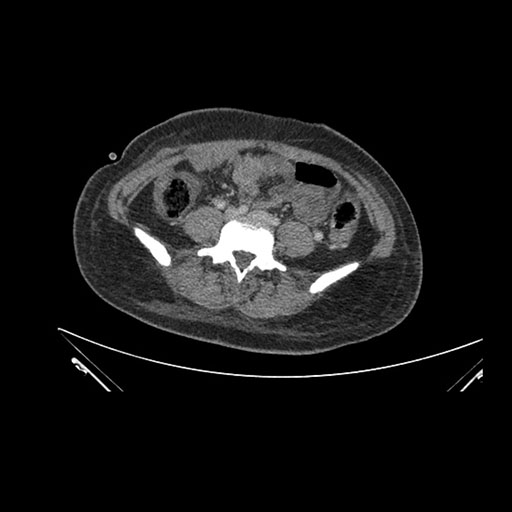

Imaging Analysis

Look through the patient's CT scan to identify any areas of concern for the necessary procedure.

Axial Venous

Based on initial findings, which issue(s) would you be most concerned about?